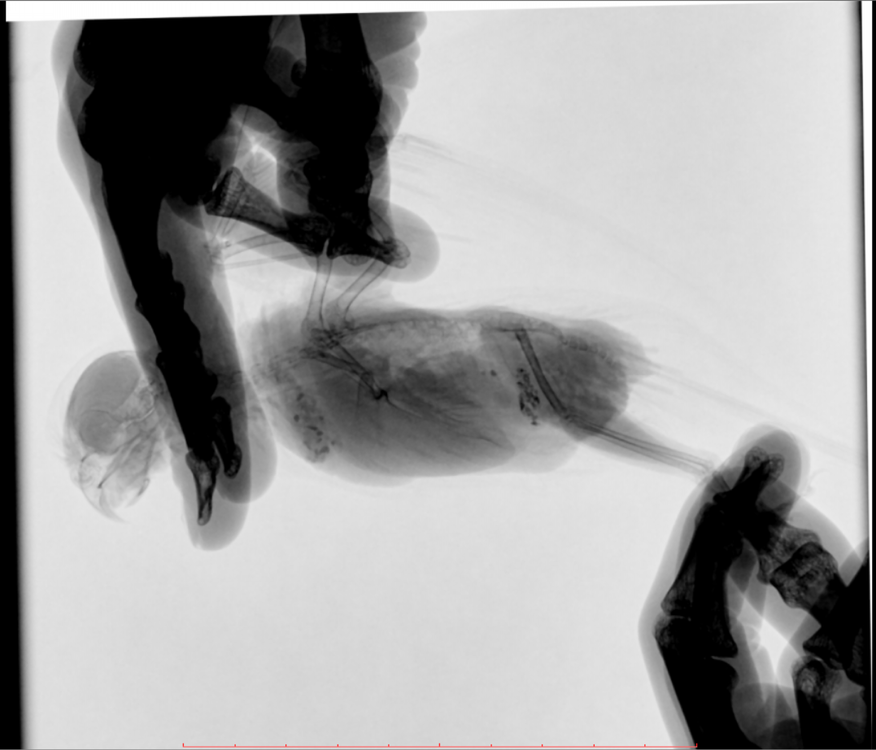

Во вторник отвозила птицу на рентген. Врач сказала, что очень сильно увеличена печень и другие органы. Также сдавлены воздухоносные мешки (из-за увеличенных внутренних органов). Отсюда - одышка. Также врач нашла перелом (старый?) ключицы. Попугая было очень сложно удерживать, поэтому снимки получились, возможно, недостаточно информативными - но какие уж получились((

@Zosia здравствуйте! Посмотрите, пожалуйста, снимки - видите ли вы на них отклонения, опухоли? Есть ли какие-то патологии? И одобряете ли вы назначенное лечение в нашей ситуации? Спасибо!

2.jpg

4.jpg

Печень видится мне увеличенной, но нужно чтобы @Zosia достоверно прочла снимки.

ответ: я увидела на снимках запущенную пневмонию, увеличенные семенники (и возможно опухоль на них), увидела в помете много палочек. Отсюда - назначение.

6.Тень семенников действительноу величена. Но снимок вами показан дурного качества. И бОльшего я сказать не могу.